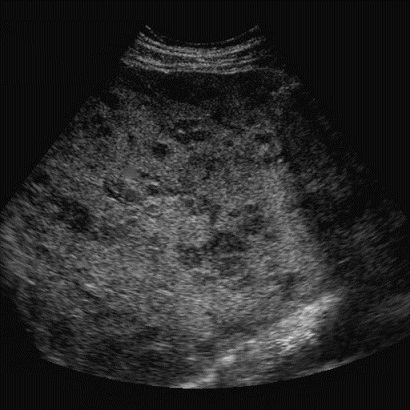

Image echographique du

carcinome hepatocellulaire : Aspect lesionaire du HCC

est une masse hyperechogene , hypoechogene ou mixte , unique

ou multiple a contour net irregulier ou mal de definissable

. Au debut , le forme plus souvent est un infiltrant a

isoechogene ,et puis sous forme nodulaire de petite

taille est hypoechogene et si en forme nodulaire de grand

taille c'est hyperechogen avec des zones necrotiques

hypoechogenes . Le " Rim sign " ou signe de "Bending sign "

le plus souvent en voyait dans HCC , ce qui en n'a pas presente

dans abces du foie . De HCC a grand taille , aspect

echographique est un masse hyperechogene multinodulaire a

contour maldefinie avec centre necrotique hypoechogene de

contenant des bougeons . Image echogaphique de thrombus de

veine porte

Image echographique de

metastase du foie : Aspect lesionaire est multiple

en nodulaire iso echogen avec contour

hypoechogen ( Bull's eye sign) |

Signe de "Bull

eye sign" des metastases du foie . Image

echographique du foie |